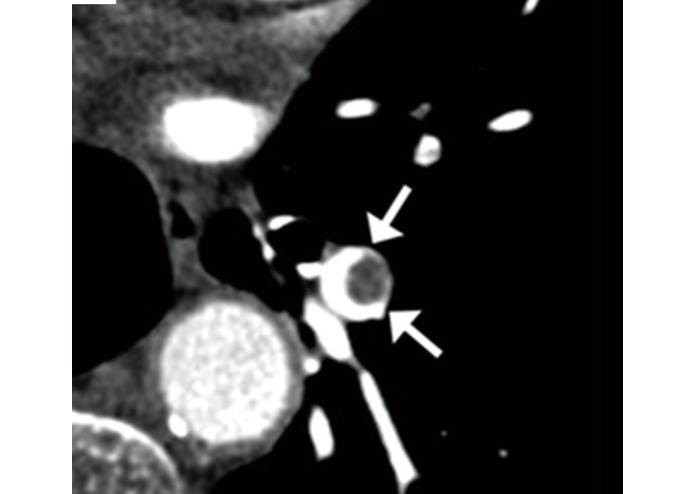

Inspired by the differnce we can make in the lives of people and the economic impact. AIMED helps detect pulmonary embolism early

We can extract just the vessel and embolus and the radiologist can only focus on those two.